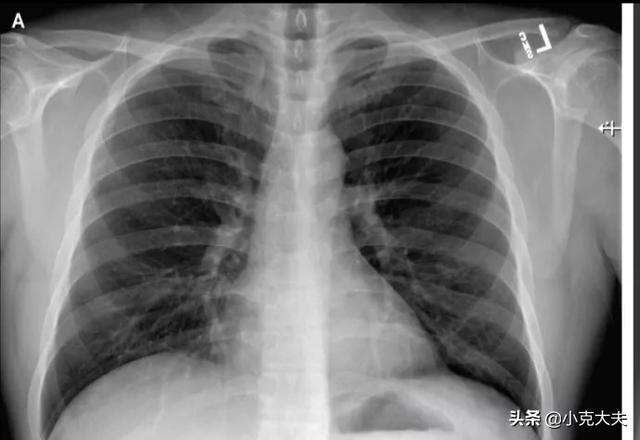

(iii) L'imagerie pulmonaire a montré une amélioration significative des lésions exsudatives aiguës ;

À l'heure actuelle, il n'existe pas de médicament spécifique pour le nouveau coronavirus, mais grâce à une thérapie symptomatique active de soutien et à une thérapie antivirale, nous pouvons bien contrôler la maladie et parvenir à la guérison. Actuellement, les critères d'isolement des contacts et de sortie de l'hôpital pour la nouvelle pneumonie à coronavirus sont les suivants : ① retour à la normale de la température corporelle pendant plus de 3 jours ; ② amélioration significative des symptômes respiratoires ; ③ amélioration significative des lésions exsudatives aiguës à l'imagerie pulmonaire ; ④ deux tests consécutifs de détection des acides nucléiques respiratoires négatifs (plus de 24 heures entre les deux tests).

La norme de guérison du nouveau coronavirus n'est pas très claire, les exigences du patient infecté sont les suivantes : après le traitement, le patient ne présente pas de fièvre, de toux sèche ou d'autres symptômes, la radiographie pulmonaire a disparu sans anomalie, le test consécutif de l'acide nucléique est négatif, mais la période de quarantaine de ces porteurs est terminée, le temps de vérifier s'il n'y a pas d'anomalie ne peut être considéré que comme exclu dans un premier temps.

Une personne infectée asymptomatique est un patient qui est infecté par le virus, mais qui ne développe pas la maladie, qui ne présente pas de symptômes tels que fièvre, malaise, toux, etc. mais dont le test d'acide nucléique est positif. Il se peut que le patient présente une bonne auto-immunité, c'est-à-dire que le système auto-immunitaire peut inhiber la croissance du virus, mais si l'immunité est diminuée, il y a un risque qu'il développe également la maladie. Les critères de guérison sont au moins deux tests d'acide nucléique négatifs, l'absence d'anomalies au scanner des poumons ou une résorption significative des lésions infectées. Après la guérison, le patient doit être isolé pendant au moins 14 jours, période pendant laquelle il doit être contrôlé à nouveau, en particulier en cas de fièvre ou de toux. Actuellement, il y a eu un cas de patient guéri à Chengdu qui s'est avéré positif lorsqu'il a été recontrôlé pour l'acide nucléique 10 jours après sa sortie de l'hôpital. Il convient donc d'être attentif.

En fait, selon le dernier "Programme de diagnostic et de traitement de la nouvelle pneumonie à coronavirus (essai, sixième édition)" publié par la Commission nationale de la santé, les critères de levée de l'isolement et de sortie des patients infectés (confirmés) par la nouvelle pneumonie à coronavirus actuelle sont spécifiés en détail : le retour à la normale de la température corporelle doit être supérieur à trois jours, les symptômes respiratoires doivent s'être nettement améliorés, l'imagerie des poumons (CT) doit montrer une amélioration significative des lésions exsudatives aiguës, et les symptômes respiratoires doivent s'être améliorés de manière significative. Sur le plan virologique, deux tests négatifs consécutifs des acides nucléiques sur des échantillons respiratoires doivent être effectués à au moins un jour d'intervalle. Si la personne infectée diagnostiquée est en mesure de remplir toutes les conditions susmentionnées, elle peut être libérée de l'isolement et mise en observation.